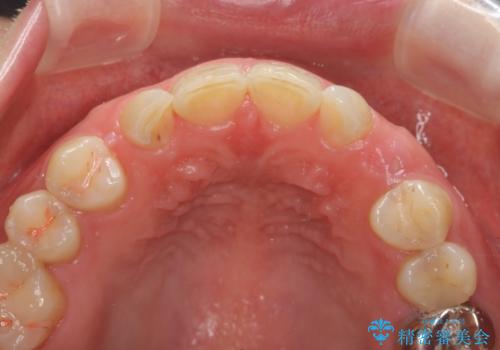

骨造成を伴う 前歯部インプラント治療

- 欠損している前歯のインプラント治療を希望され来院されました。

適切なインプラント埋入を行い、不足している骨量を補うため骨の造成を併用したインプラント治療を計画します。

前歯のインプラント治療は骨量・歯肉の厚み・インプラントの方向をしっかりと計画することで、審美的で長持ちを期待できるような仕上がりとなります。